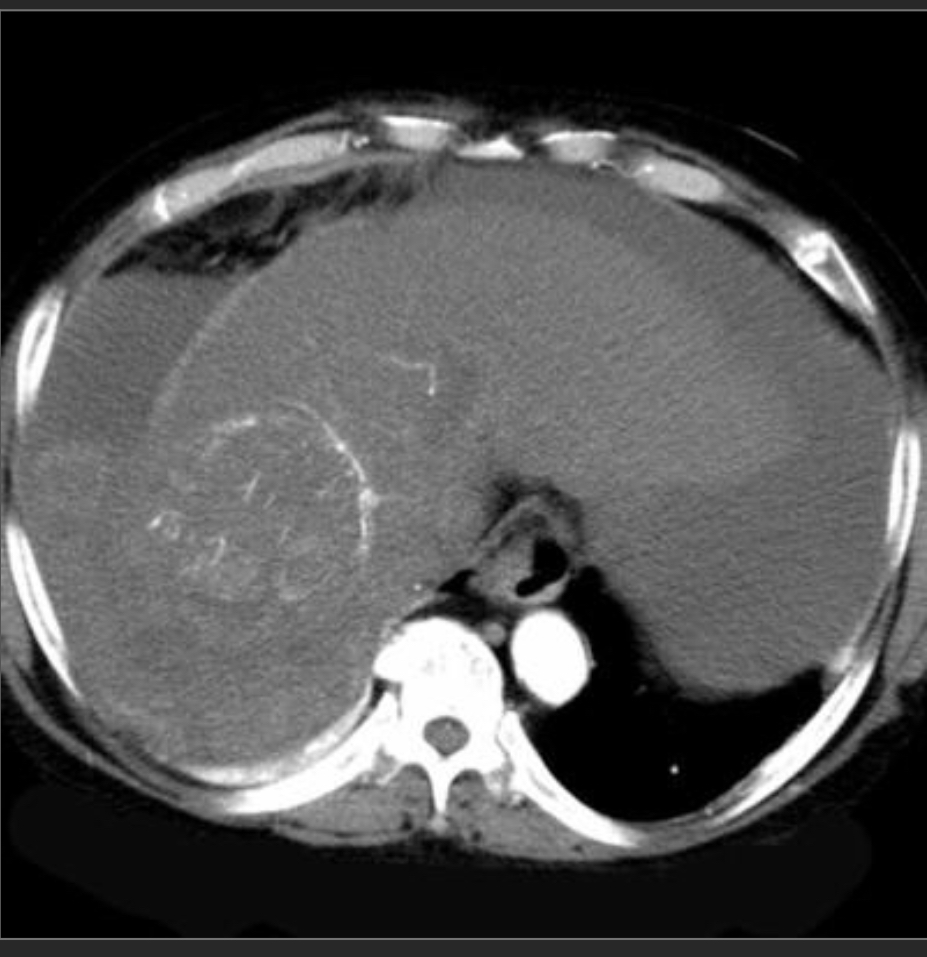

Incidentally seen liver lesion.

Isodense to liver on other phases

FNH

homogeneously hypervascular on arterial phase imaging and nearly isodense to liver on other phases; the additional presence of a central scar is essentially pathognomonic.

—> in a younger woman w/o hx of cancer, can be dx from the CT appearance

—>hemangioma would be hypervascular but isodense to vessels, not liver.